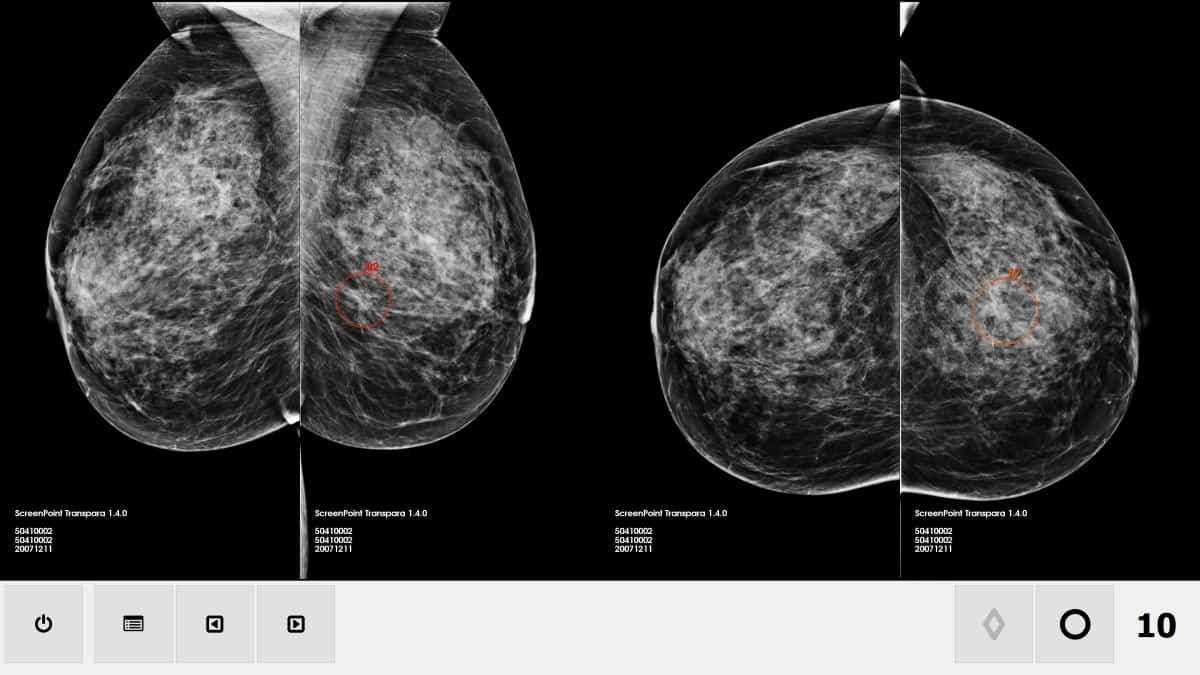

5️⃣ 🥇 1순위 붕괴 영역: 진단

왜 진단이 가장 먼저 무너질까?

진단은 겉보기와 달리 고도의 패턴 인식 작업입니다.

- CT·MRI·X-ray → 이미지 데이터

- 혈액·유전자 검사 → 수치 데이터

- 진료 기록 → 텍스트 데이터

👉 AI가 가장 잘하는 분야입니다.

이미 벌어진 현실

- 영상의학과 판독 AI: 오진률 감소 사례 다수

- 피부암·유방암·폐암 스크리닝: 전문의 수준 이상

- 응급실 트리아지: AI 우선순위 판단 도입

🔎 확실한 사실

다수 국가에서 AI 단독 진단은 제한되지만,

AI + 의사 모델은 이미 표준화 단계입니다.

결정적 차이

- 인간: 컨디션·피로·경험 편차

- AI: 24시간 동일 성능

➡️ 진단 영역에서는 이미

“누가 더 안정적인가”의 싸움이 끝났습니다.